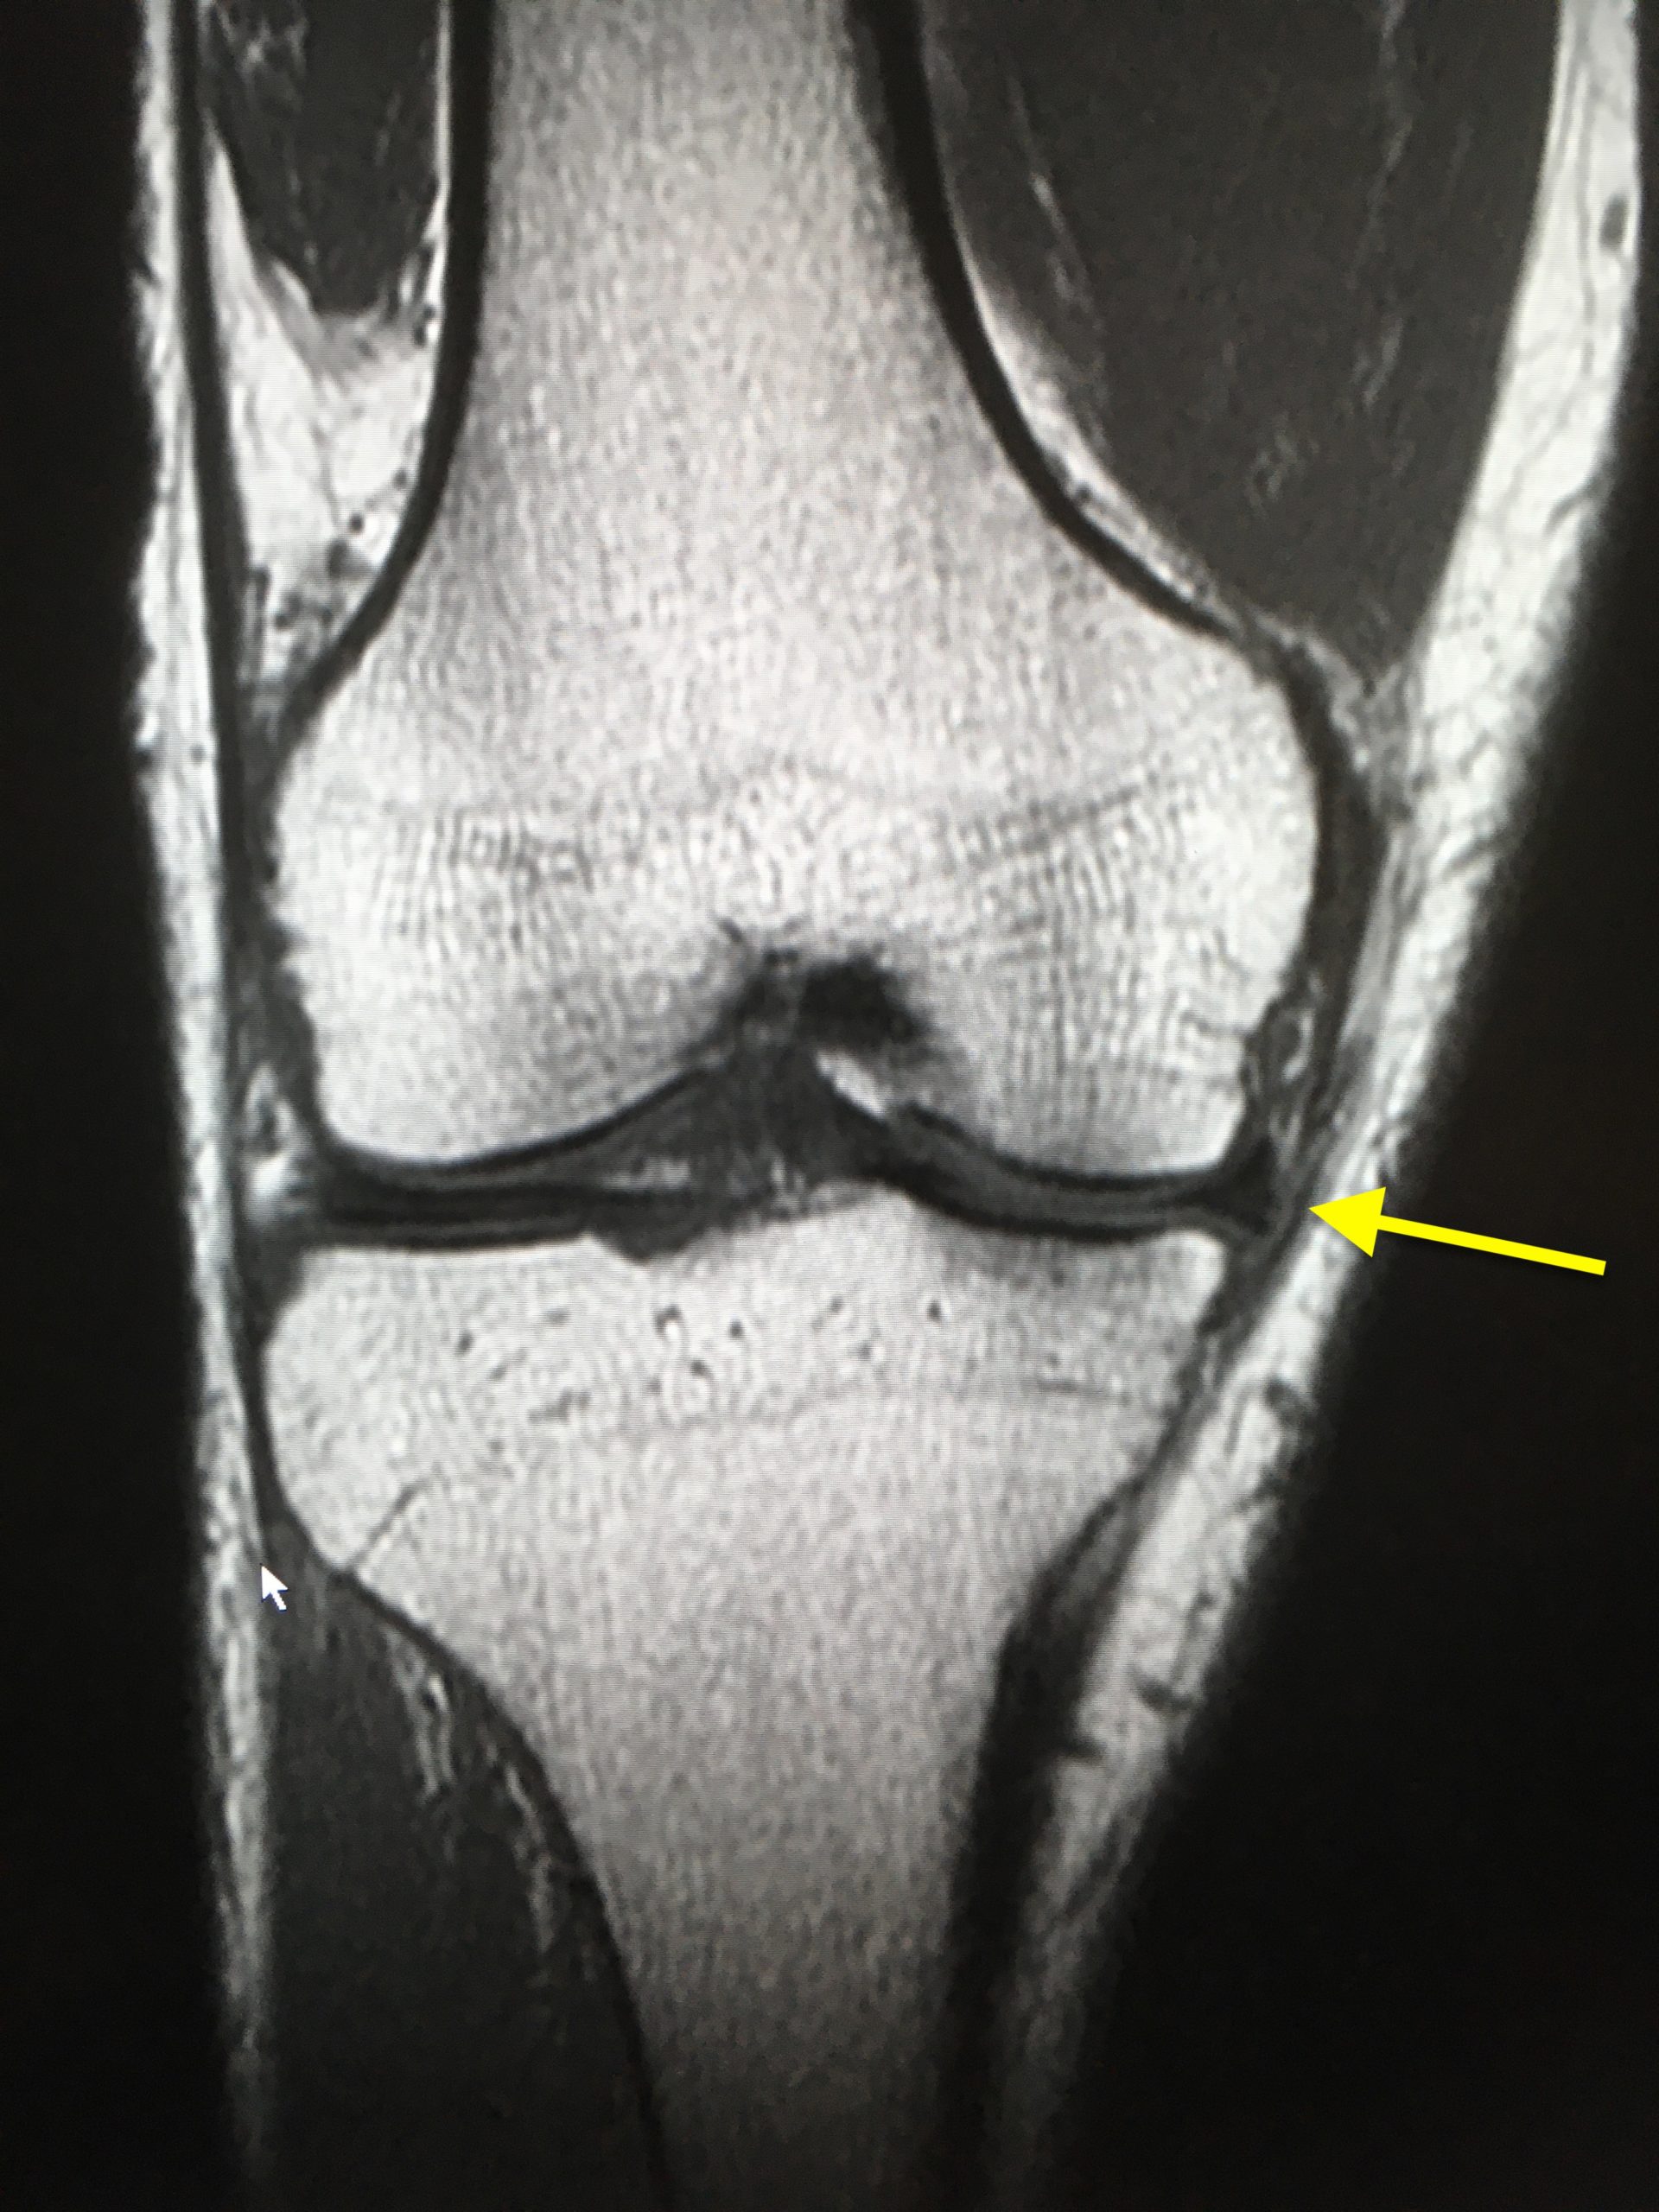

半月 板 嚢腫

膝関節メニスクスガングリオン 半月板嚢腫 の1例 臨床整形外科 16巻12号 医書 Jp

半月板嚢腫の病態と治療法 関西関節鏡 膝研究会誌

半月板嚢腫を伴った両側内側円板状半月板の1例 臨床雑誌整形外科 63巻10号 医書 Jp

半月板嚢胞 かけだし放射線科医 日々の記録

半月板嚢胞に伴う骨溶解の頻度と特徴は こぼうず 画像診断医 Note